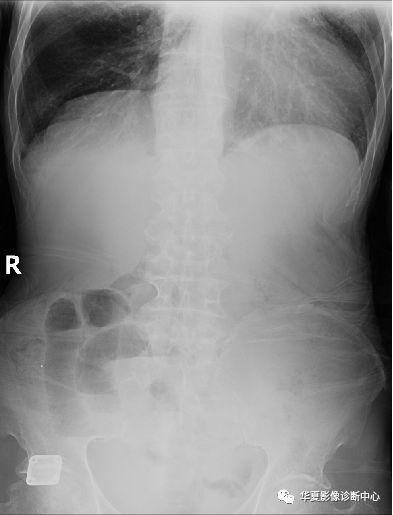

腹部气液平面x线图片

正常腹部x线图片